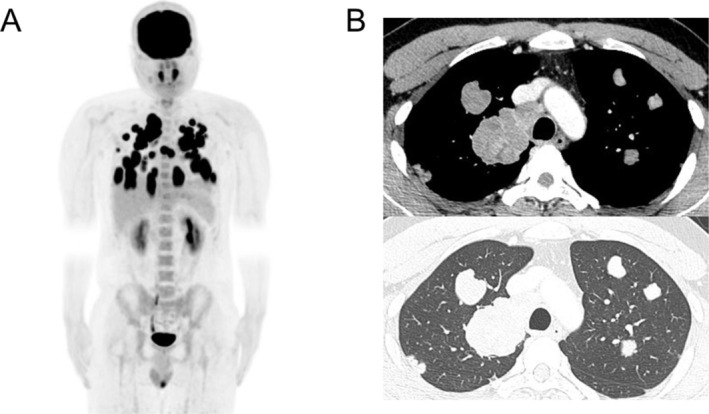

Extra-adrenal paraganglioma is a rare tumor and is difficult to diagnose. We report a case of extra-adrenal paraganglioma in the hilum identified after treatment for multiple intrathoracic lymph node metastases from testicular cancer. A 32-year-old man presented to the hospital with a cough. Computed tomography revealed multiple lung tumors and intrathoracic lymph node swelling. The patient was diagnosed with left-sided testicular cancer with multiple intrathoracic metastases. A left orchiectomy was performed, followed by chemotherapy. A lung biopsy confirmed the absence of residual cancer. Three months after the lung biopsy, 18F-fluorodeoxyglucose positron emission tomography/computed tomography revealed fluorodeoxyglucose uptake in the right hilum. Suspecting lymph node metastasis from testicular cancer, we performed tumor resection. Pathological findings diagnosed the lesion as a paraganglioma. Diagnosing extra-adrenal paraganglioma hidden by a primary tumor is highly challenging without complete remission of the primary tumor.